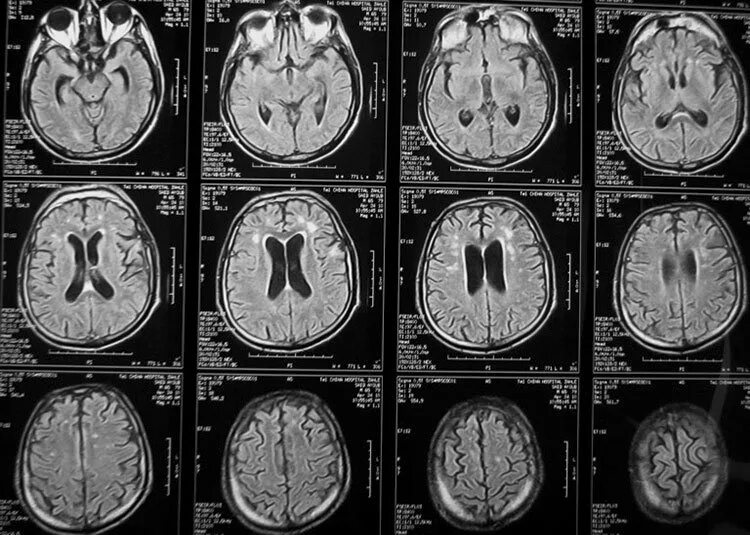

Томограмма головы